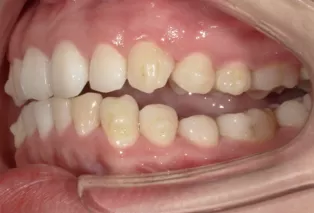

Photos intra-orales